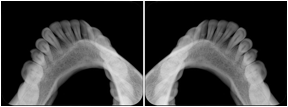

Intra-oral radiography typically involves acquisition of multiple images of various parts of the dentition. Many digital radiographic systems offer customized templates that are used for displaying the images in a study on the screen. These templates may also be referred to as mounts or view sets. The Structured Display Object represents a standard method of encoding and exchanging the layout and intended display of Structured Displays. A structured display object created in this manner could be stored with a study and exchanged with images to allow for complete reproduction of the original exam.

1. A patient visits a General Dentist where a Full Mouth Series Exam with 18 images is acquired. The dentist observes severe bone loss and refers the patient to a Periodontist. The 18 images from the Full Mouth Series along with a Structured Display are copied to a DICOM Interchange CD and sent with the patient to see the specialist. The Periodontist uses the CD to open the exam in his Dental Radiographic Software and consults via phone with the General Dentist. Both are able to observe the same exam showing the images on each user's display using the exact same layout.

Intra-oral Full Mouth Series Structured Display

Figure OO-1. Intra-oral Full Mouth Series Structured Display